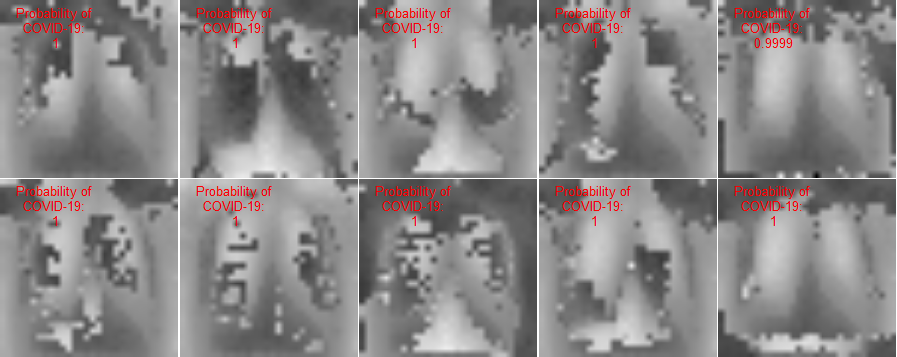

This section presents visualization of the proposed architecture. These visualizations are presented in Figure 5. Unlike Figure 2 that is an executive summary with each position representing many samples, these visualizations in Figure 5 are sample-wise plots. In other words, the 10 original images that are sized 128 by 128 in Panel A and Panel B are the same samples in the second row, 1st Conv. Layer, and the third row, 2nd Conv. Layer.

Visualization Interpretation The plot in Figure 5 of the original images for COVID-19 patients has grey and cloudy textures in chest area. Because an X-ray picture is at its brightest when most of the light beams emitted are bounced back from the object, we can observe bones to be the color “white” while the margin to be completely “black”. For muscle and organs inside human body, X-ray beams that are emitted can only partially be collected and this causes the greyscale on the X-ray images in chest area. For COVID-19 patients, there are grey and shaded area in the chest X-ray pictures. This is due to the inflammatory fluid when patients exhibit pneumonia-like symptoms. The fluid inside chest area is a consequence of human immune system fighting against outside diseases. This shaded (as seen in Panel A of Figure 5) prevents us from observing the clear location of lungs. This is different in Panel B where the lung areas are dark and almost black, because a healthy lung is filled with air (i.e. normal cases and X-ray image presents color black). The black and white contrast in the two panels is directly related to how much inflammatory fluid there is in human lungs. This contrast translates to greyscale on pictures and it is directly related with COVID cases and non-COVID cases (i.e. response variable ). The same contrast can be seen using the new variables (these are ’s based on equation 4) in the 1st Conv. Layer (sized 61 by 61). For COVID-19 patients, the lung area is cloudy and unclear while the healthy cases it is clearly visible. This is not a surprising coincidence because the proposed new variable modules, ’s, are engineered using equation 4 which relies on the response variable in training set. The images sized 61 by 61 from the proposed algorithm is a direct translation of not only the original pixels but also response variable. In other words, this visualization presents how I-score sees image data.

| 2nd Conv. Layer: 30 by 30 | 2nd Conv. Layer: 30 by 30 | |

| (Starting Point = 6, Window 2 by 2, Stride = 2) | (Starting Point = 6, Window 2 by 2, Stride = 2) | |

| Remark: variables | variables | |

| Same 10 images above with 900 variables | Same 10 images above with 900 variables | |

| Labels predicted using Model 4 | Labels predicted using Model 4 | |

| Row (c) |  |

This figure presents visualization summary for 10 randomly sampled images from COVID class and non-COVID class (each has 10). Panel A is for COVID patients and Panel B is non-COVID people. The first row plots the original images that are sized 128 by 128. The 1st Conv. Layer generates new variables. We plot the same 10 images from both classes using these 3,721 variables in the second row. We also print the predicted COVID probabilities on top left corner of each image. The 2nd Conv. Layer generate variables. We plot the same 10 image samples from both classes using these 900 variables in the third row. We also print the predicted COVID probabilities on top left corner of each image assuming using only these 900 variables as predictors. The plot of the original images for COVID-19 patients has grey and cloudy textures in chest area. This is due to inflammatory fluid when patients exhibit pneumonia-like symptoms. This shaded (as seen in Panel A) prevents us from observing the clear location of lungs. This is different in Panel B where the lung areas are dark and almost black which means the lung is filled with air (i.e. normal cases). The black white contrast in the two panels is directly related to how much inflammatory fluid there is in human lungs which translate to greyscale on pictures. The same contrast can be seen using the new variables (these are ’s based on equation 4) in the 1st Conv. Layer (sized 61 by 61). For COVID-19 patients, the lung area is cloudy and unclear while the healthy cases it is clearly visible.

1st Conv. Layer. to 2nd Conv. Layer. From the resulting matrix of the 1st Conv. Layer, we are left with 3,721 variables. We go through the proposed design in Table 4 and we create a new convolutional layer, i.e. 2nd Conv. Layer. This new layer has variables. We take the same 10 sampled images from before and we use these 900 variables to present these images. In this presentation, we resize these 900 variables into shape 30 by 30. In other words, we get a smaller matrix that we can plot that exhibit mini version of similar patterns as before. We use Model 4 to generated the predicted probabilities. These probabilities are printed on the top left corner of each image and they are color coded similarly as before (red probabilities have ground truth of COVID class while green probabilities have ground truth of non-COVID class).